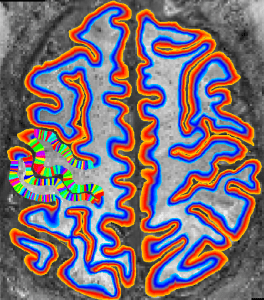

Description: Collection of C++ programs developed from Renzo Huber that operate exlusively in voxel-space.

Advantage: Because I wrote it myself, I know what it does and how the algorithms work 😉 Very flexible and application for real-life data with limited FOV. Since its implemented in C++, its super fast.

Disadvantage: Some functions are using ODIN libraries for the reading and writing of Nifties, which requires a unix machine with root access to be installed This requirement is not easily fulfilled in all labs

I didn’t transfer all the programs to a NIFTI I/O to a standalone C++, just yet. Hence, many programs still depend on ODIN libraries and are only applicable on UNIX machines. The equi-volume layering is still not optimized for oblique slices that are curved in 3D.

It does not have a very robust tissue segmentation algorithm, yet. So I need to use alternative methods and manual corrections.